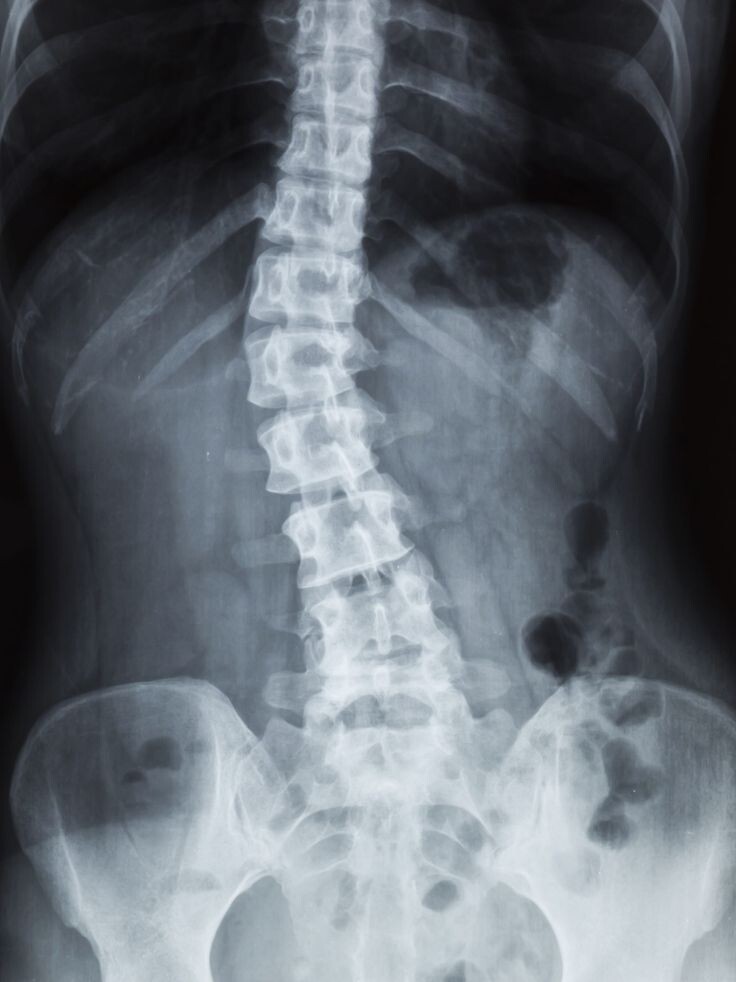

Сколиоз — это боковое искривление позвоночника во фронтальной плоскости . Простыми словами: позвоночник уходит вправо или влево, образуя дугу.